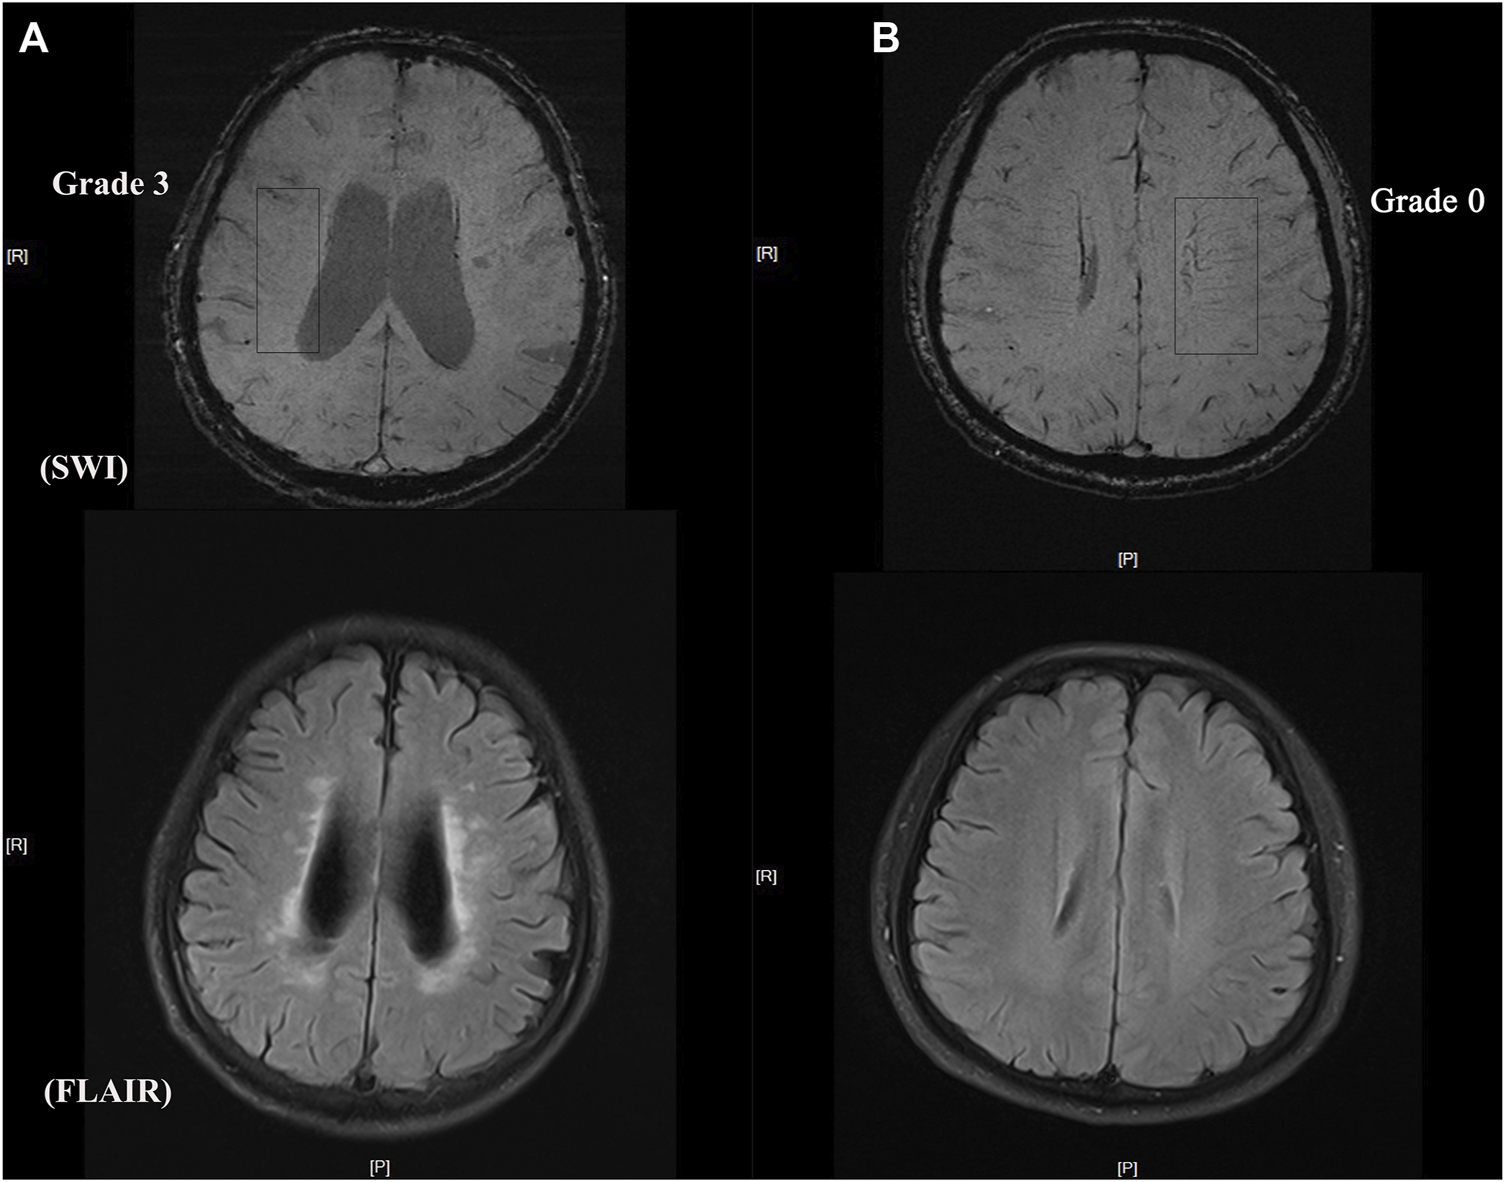

2.5 Measurement of DMV

The number of DMVs was assessed visually using SWI based on a brain region-based DMV visual score protocol (Zhang et al., 2017) by two trained neurologists (HL and WRT) who were blinded to all clinical data. Briefly, a region of interest from the level of the ventricles immediately above the basal ganglia to the level of the ventricles that immediately disappeared was selected in each cerebral hemisphere. Three regions (frontal, parietal, and occipital) were identified in each region of interest according to the DMV anatomy. DMVs crossing a region of interest were quantified using a four-point grading scale (Grade 0: each vein was continuous and had a homogeneous signal; Grade 1: each vein was continuous, but one or more veins had an inhomogeneous signal; Grade 2: one or more veins were not continuous and presented with spot-like hypointensity; Grade 3: no observed vein was continuous). The total number of DMVs was the sum of the grades for the three regions in each hemisphere. Representative images of DMV are shown in Figure 1.

FIGURE 1

Representative images of DMV and CSVD burden (A) DMV score = grade 3 with heavy white matter hyperintensity burden (B) DMV score = grade 0 with light white matter hyperintensity burden.